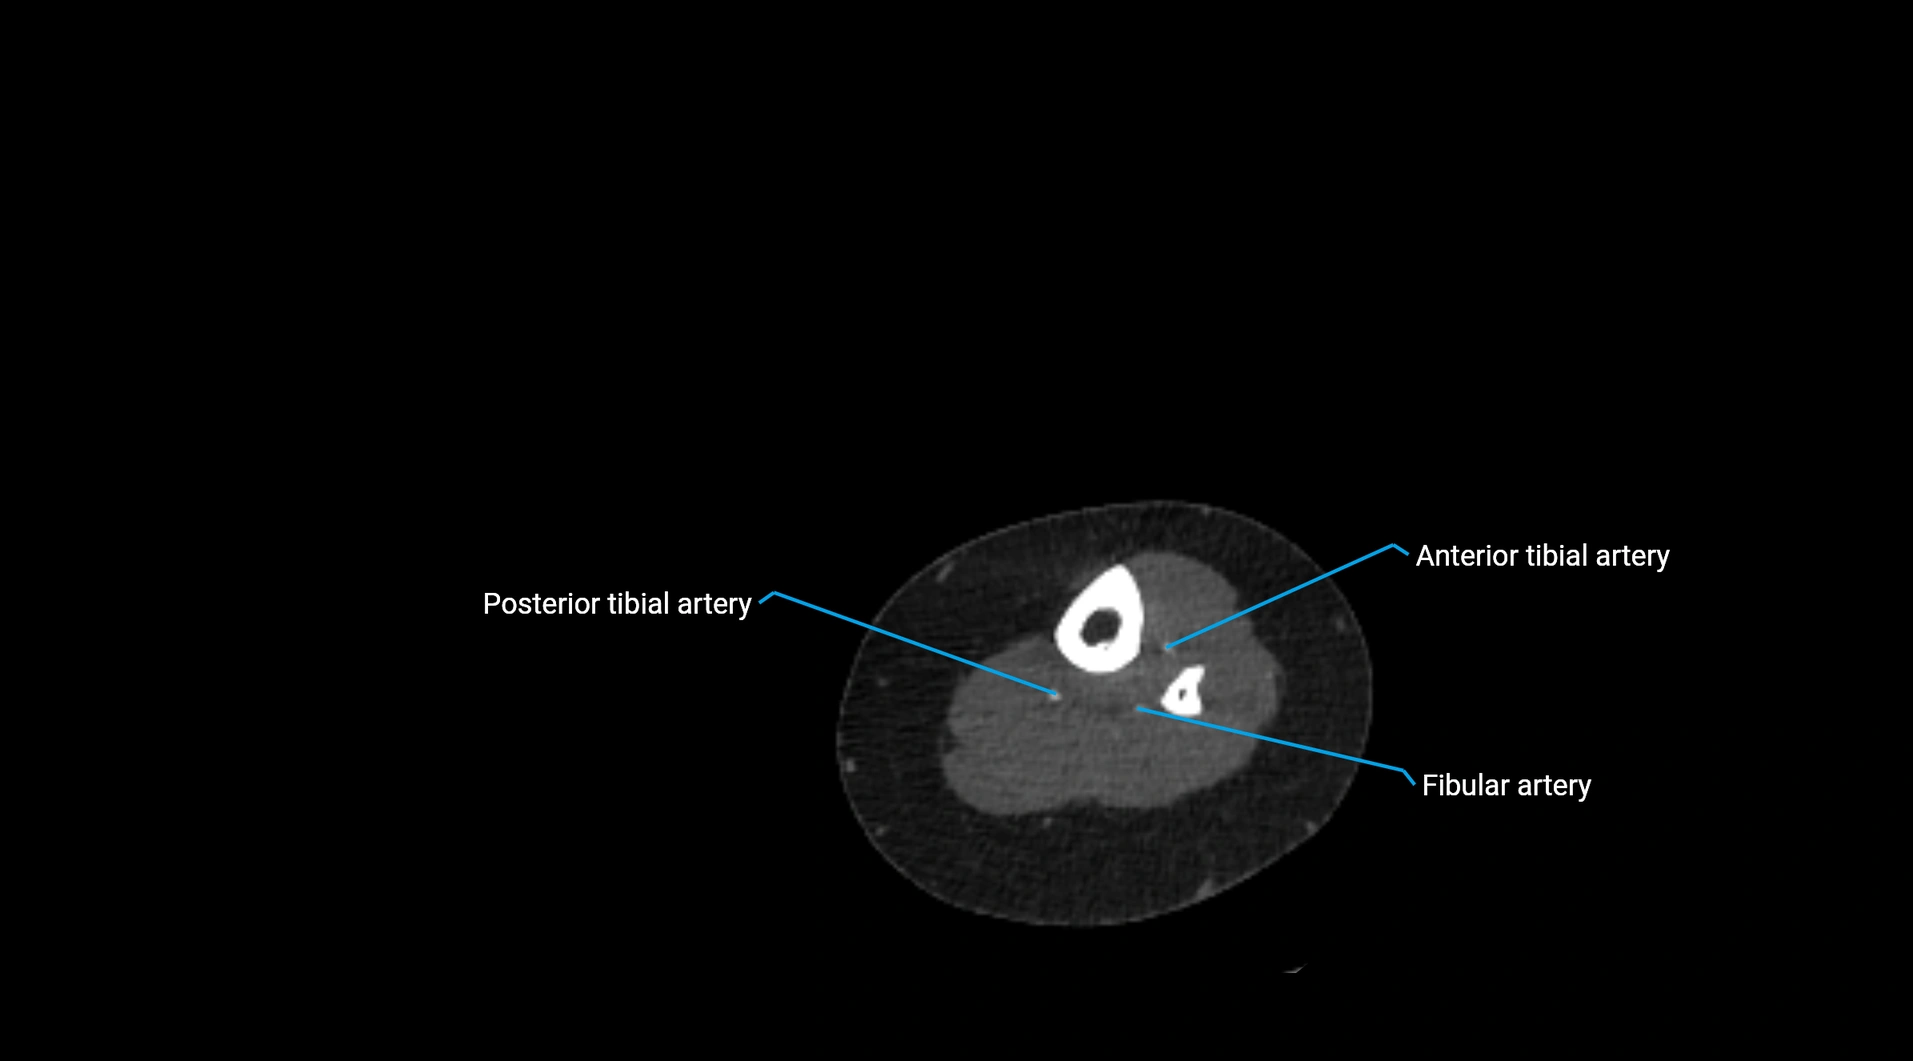

CT images

image

Contrast-enhanced CT (CTA):

• Gold standard for abdominal aortic imaging

• Provides excellent detail of lumen, wall, aneurysm, thrombus, and branch vessels

• Multiplanar and 3D reconstructions help in aneurysm measurement, stent graft planning, and dissection evaluation